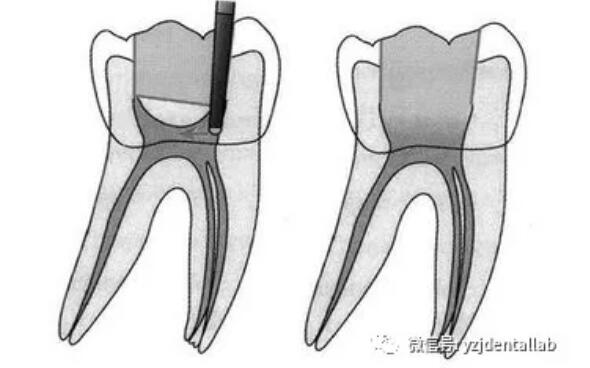

、開(kāi)髓去腐質(zhì)

去凈腐質(zhì)和原有充填物、揭凈隨頂,看到整個(gè)髓底解剖結(jié)構(gòu)、髓壁與根管壁連續(xù)流暢、沒(méi)有牙頸部臺(tái)階,沒(méi)有過(guò)度切割髓壁和髓底以便后續(xù)治療順利進(jìn)行。

開(kāi)髓步驟:

局麻--上橡皮障--去除所有腐質(zhì)--接髓頂--形成與根尖孔1/3的直線。

開(kāi)髓的質(zhì)控標(biāo)準(zhǔn):

a、去凈腐質(zhì)和原有充填物。

b、揭凈髓頂,看到整個(gè)髓底解剖結(jié)構(gòu)。

c、髓壁與根管壁連續(xù)流暢。

d、沒(méi)有牙頸部臺(tái)階,沒(méi)有過(guò)度切割髓壁和髓底。